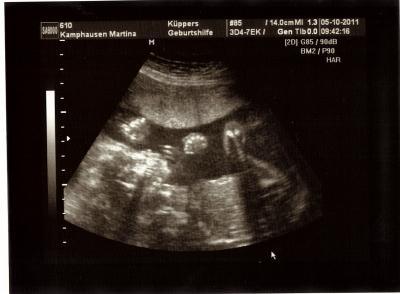

So Ihr Lieben. Ich bin zurück von meinem FA Termin. Es war toll. Der 2. US stand an und der kleine Mann hat sich super gezeigt. Er liegt zur Zeit noch BEL, aber das ändert sich ja noch ständig. Mittlerweile ist er 22 cm groß und zeitgerecht entwickelt. ET musste somit nicht geändert werden. Ach ja. Insgesamt hab ich nun 8,6 kg zugenommen.

Bild zu Hatte heute Termin beim Gyn. - Forum für Februar - Mamis